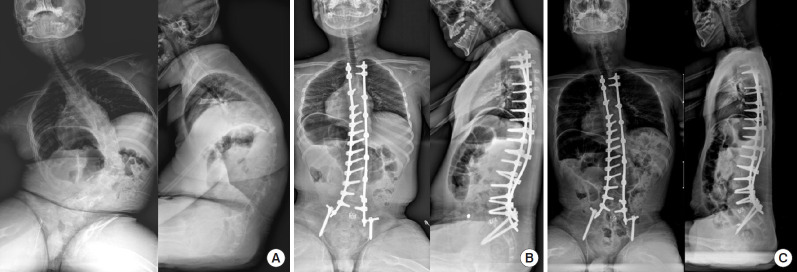

Changes in the surgical fixation system from wire, hook, or hybrid instrumentation to pedicle screw-only instrumentation also made the posterior correction of curve more effective. Posterior-only surgery appears to lead to comparable radiological results (overall Cobb correction of 54% in the posterior-only group and 50% in the anterior-posterior group). This included shorter operation times and shorter intensive-care unit and hospital stays than the combined anterior-posterior instrumentation in patients with severe CP [8]. Shao et al. [9] performed a metaanalysis and described that the posterior-only approach is similar to the anterior-posterior approach for the correction of scoliosis in coronal and sagittal planes. However, the anterior-posterior approach has advantages of correcting pelvic obliquity and decreasing the loss of angle between postoperation and follow-up in the main scoliosis. In contrast, the posterior-only approach has the advantage of decreased operation time, blood loss, duration of hospital stay, and complications. The traditional anterior approach needs a wide incision or longer operation time. However, in our opinion, advanced anterior operation, such as oblique lateral interbody fusion, may be an alternative surgical option in selected cases (Fig. 2).

Fig. 2.

(A) A 15-year-old girl with muscular dystrophy had 56° (T6–T12) of neuromuscular scoliosis in the posteroanterior whole spine radiography in the sitting position. (B) She underwent L5/S1 oblique lateral interbody fusion and posterior instrumentation from T1 to the pelvis. (C) Pelvic obliquity was successfully corrected and maintained until the postoperative 6-year follow-up.

The simple comparison between these 2 studies is inappropriate because Takaso et al. [31] included only flaccid neuromuscular scoliosis. In contrast, the patients in the study by Tøndevold et al. [32] had a different etiology (52% of CP, 12% of central motor neuron involvement, 10% of SMA, and others). The advantage of the mobile L5–S1 disc space may be the absorption of stress during wheelchair activities, sitting on the floor, or crawling. Although the fixation to L5 in patients without severe pelvic obliquity has not achieved wide acceptance, it certainly merits strong consideration, particularly with early diagnosis and adequate counseling of the family before the curves become severe and rigid (Fig. 3) [33]. In a recent review article, fusion short of the pelvis was considered in patients with adequate head control without the presence of hip subluxation or dislocation and when pelvic obliquity is < 15° [34]. In our opinion, if pelvic obliquity is associated with coronal imbalance, especially C-type neuromuscular scoliosis, pelvic fixation should be performed considering the correction of the curve and postoperative coronal balance.

Fig. 3.

(A) A 12-year-old girl with spastic quadriplegic cerebral palsy underwent posterior instrumentation from T2 to L5. She underwent hip reconstructive surgery 3 years ago. Preoperatively, hip joint was stable and L5 tilt on pelvis was not prominent, although pelvic obliquity on sitting position was severe. She was very thin (38 kg), and had a gastrostomy tube and sore on coccyx. Because of the possibility of postoperative infection, fusion was stopped at L5. Pelvic obliquity improved after operation, but the remaining pelvic obliquity was slightly progressed at the 12-month follow-up. However, the patient and parents did not complain of any discomfort during sitting. (B) A 17-year-old boy with spastic quadriplegic cerebral palsy underwent posterior instrumentation from T3 to the pelvis. Pelvic obliquity was improved and maintained during the 5-year follow-up.